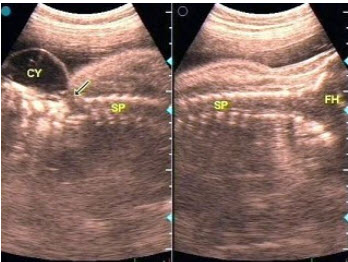

18、单项选择题

某患者左肾超声声像图如下,最可能的诊断为()

A.多发性肾囊肿

B.肾结核

C.多囊肾

D.重度肾积水

E.中度肾积水